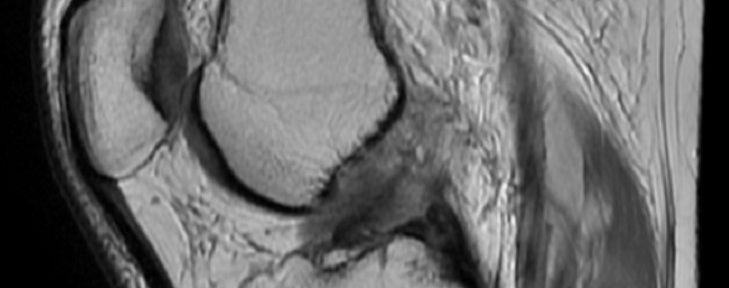

2022年2月26日にスキー中に左膝を捻った。MRI撮影により以下の診断を得た。

前十字靭帯完全断裂

2022年11月18日に2回目のMRIを受けた結果、前十字靭帯の明瞭な連続性が示された。この治癒タイプはIharaの治癒分類のグレードIに分類され、引き締まった直線型の治癒形態とされている。